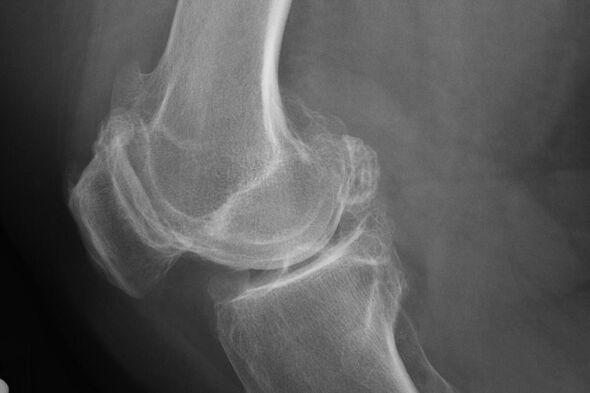

In der Regel tritt die Diagnose der Krankheit in diesem Stadium durch Zufall während eines X -Streits auf. Darauf kann der Arzt einige Unregelmäßigkeiten auf Knorpel bemerken. Es ist auch möglich, das Lumen zwischen den Teilen der Verbindung zu verengen.

X -Ray hilft dabei, Abweichungen im Knorpel zu identifizieren.

Nach der Untersuchung verschreibt der Arzt die Patient -Radiographie. Dies ist die Hauptmethode zur Diagnose der Arthrose des Kniegelenks eines beliebigen Grades.

X -Ray gibt dem Arzt eine Vorstellung von den Veränderungen im Knorpel des Gelenks. In einigen Fällen kann die Anfangsphase jedoch nicht im Bild definiert werden.

Bei Bedarf kann der Arzt einen wiederholten Durchgang einer Röntgen- oder Rechen- und Magnetresonanztomographie verschreiben.